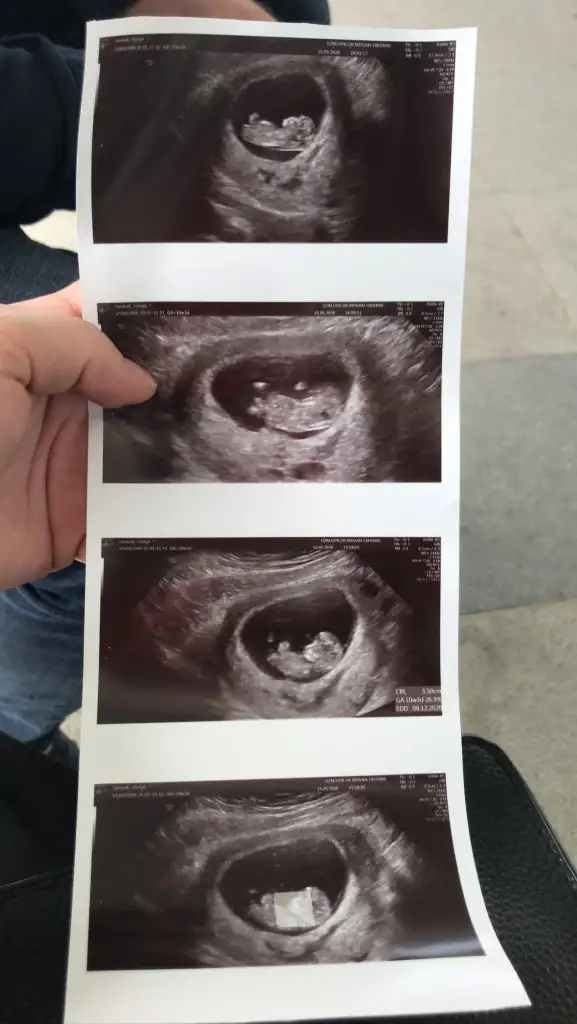

kızlar doktordan geldim çok şükür büyümüşüz normal dedi doktor herşeyine ikili test için kan da verdim haftaya çıkacak inşallah Rabbim kucağımıza almak nasip etsin Tahmin yapıyordunuz atıyorum fotoyu Eki Görüntüle 2635593